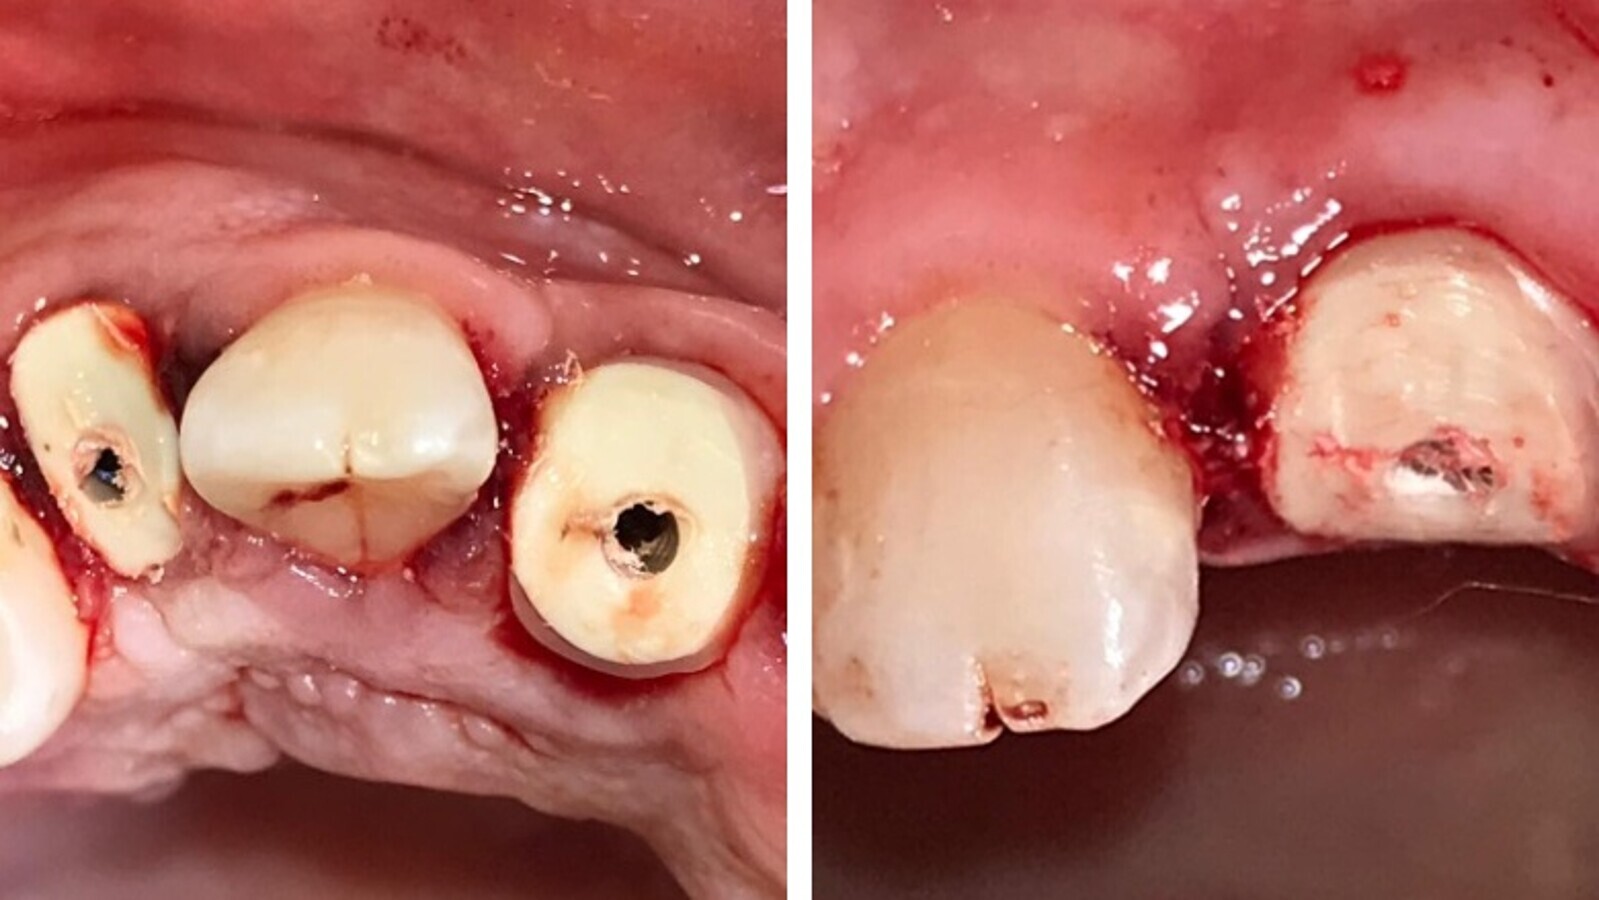

Pasados 90 días se procede a la activación de los implantes colocándoles perno muñones con tornillos pasantes y piezas provisorias.

Fig. 10. Estado gingival con provisorio colocado en pieza 13 y perfil y perno muñón en pieza 11.

Fig. 11. Estado gingival de otro caso tratado por agenesia de 12 y 22, con implantes sin Sculgar.

Fig. 12. Imágenes mostrando el estado gingival a 90 y 150 días después de la activación aun con provisorios.